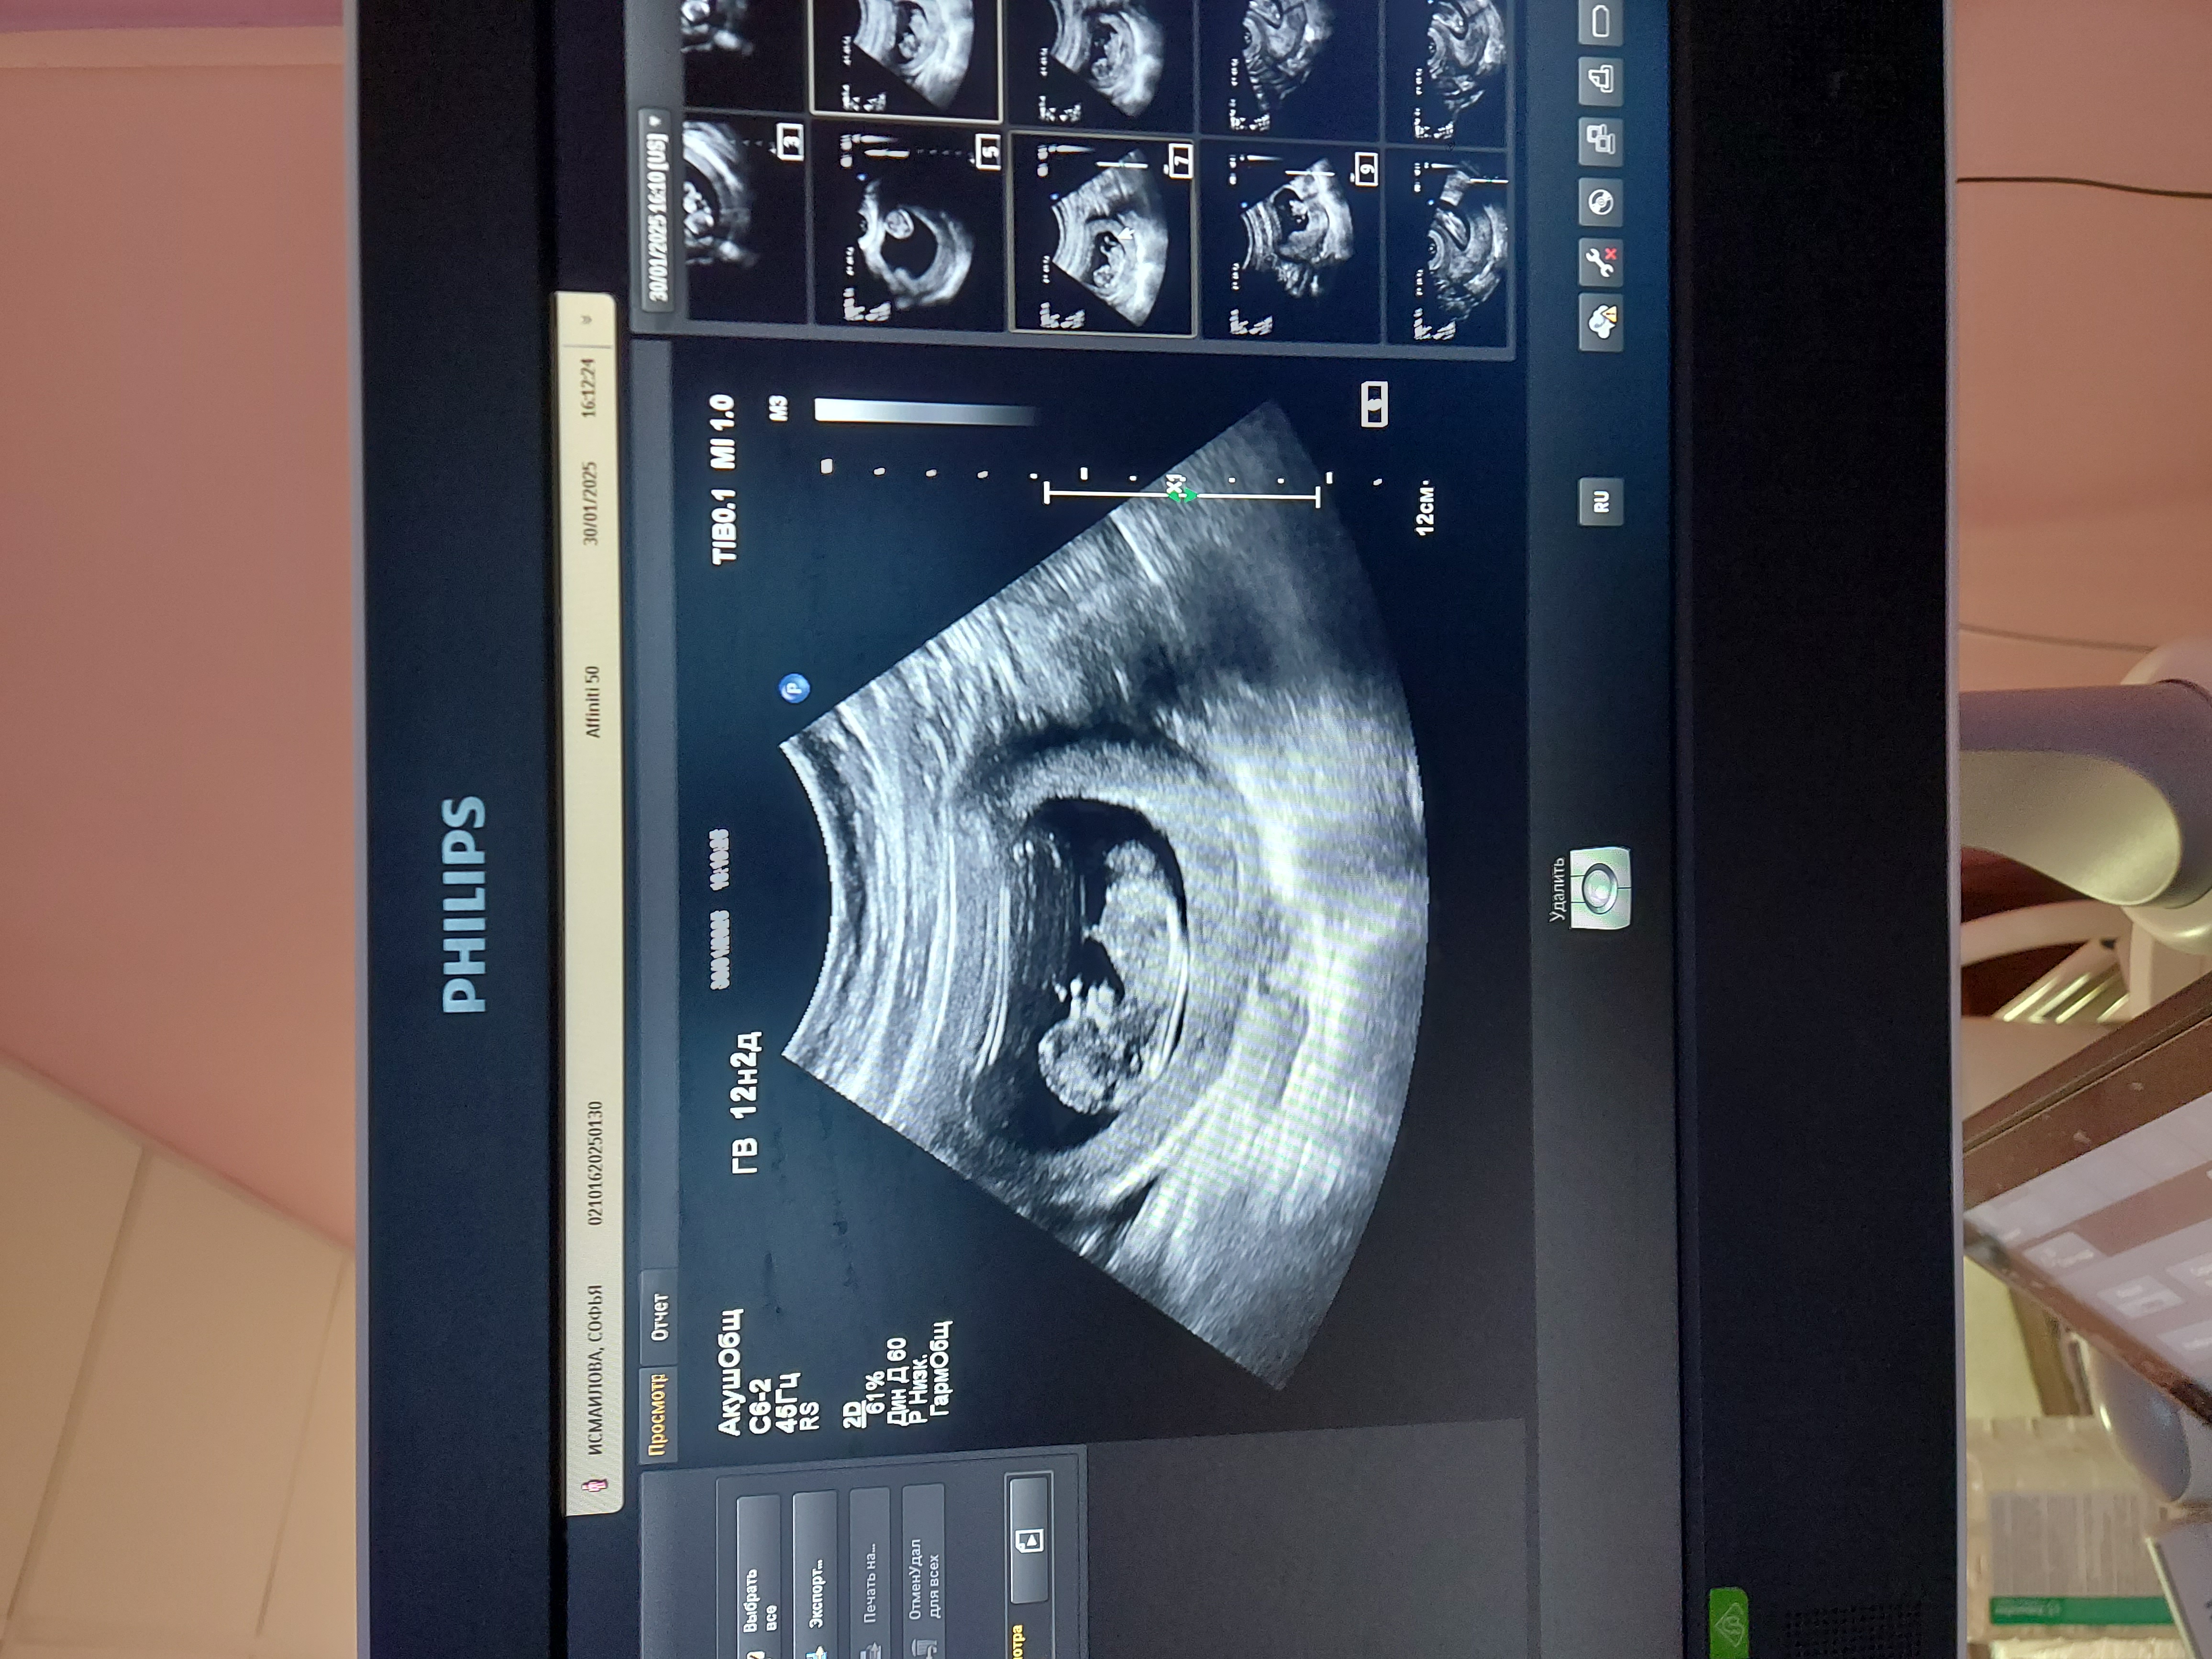

Екатерина, показался либо молчаливым, либо серьёзным) А так всё по делу сказал и объяснял все показатели. Пришла рановато (на 11 неделе), так что трудно ему было разглядеть свод черепа, мой врач через неделю смотрела. Вот на счёт пола, он вообще ничего не сказал, но там и не видно было особо. Только на 20 неделе сказали, на 2 скриннинге. Во второй раз юыда женщина, очень приятная, разговорчивая и улыбчивая. Конечно она больше понравилась. Но Сушин как специалист не плохой, как мне показалось. Вы главное не переживайте, думаю у вас всё будет в порядке😊

Малышарик прячется Определение пола на 15 неделе